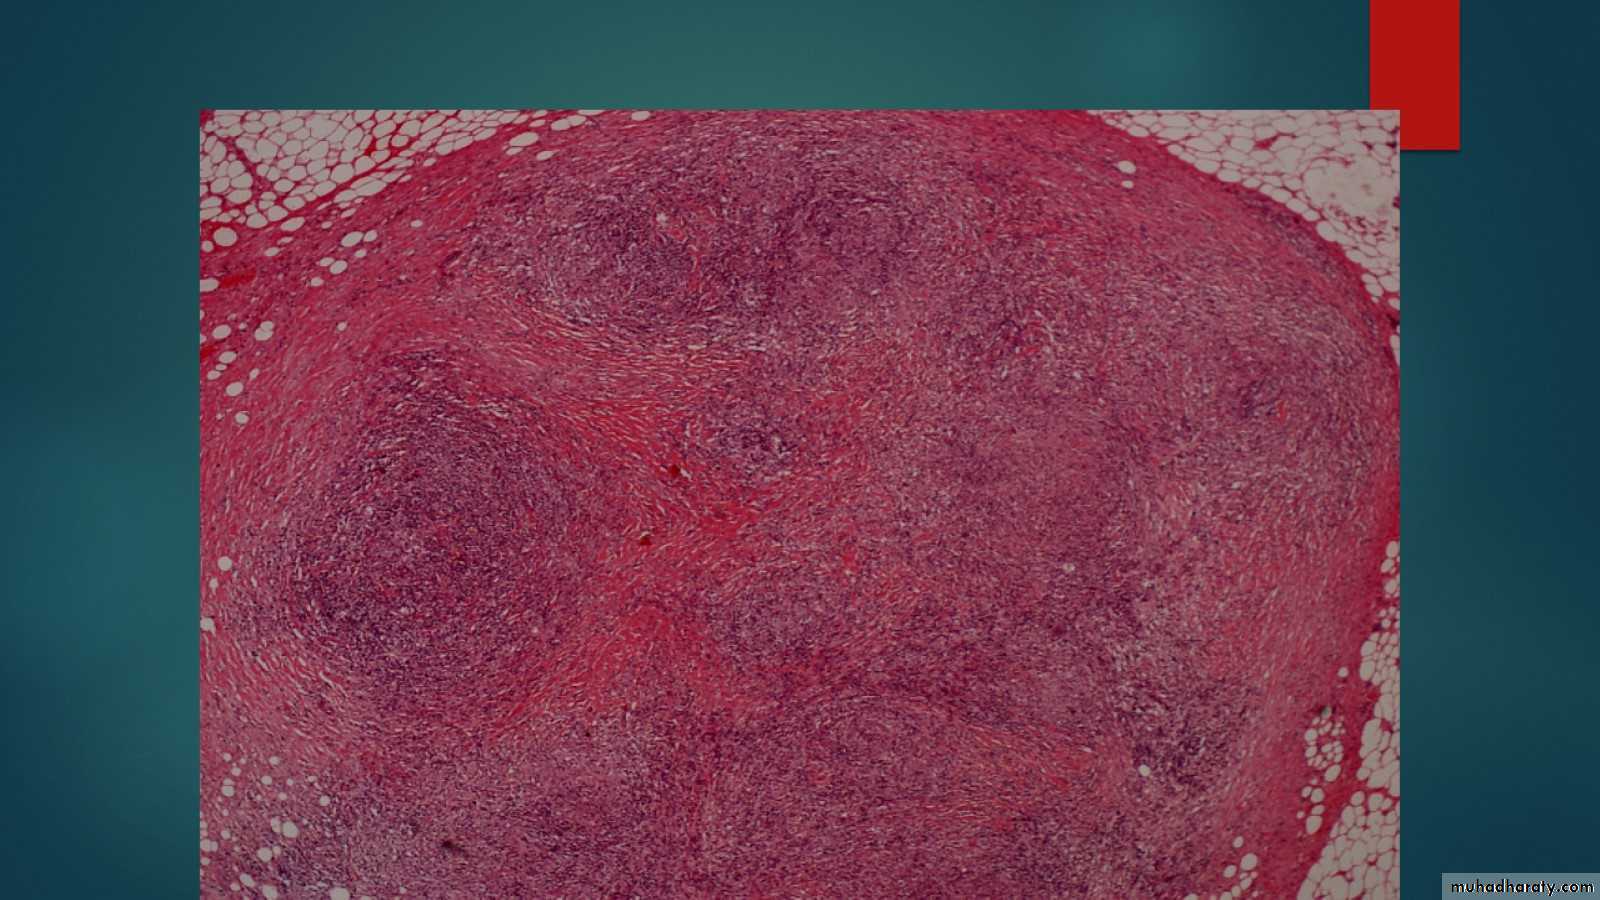

Follicular hyperplasia lymph node LP mic